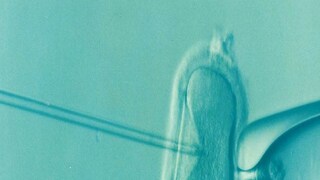

২. এই ডিম্বাণু পুনরুদ্ধারের জন্য প্রস্তুত হয়। এর পর একটি আলট্রাসাউন্ড প্রোবের মাধ্যমে ডিম্বাণুগুলি অ্যাসপিরেট করা হয়। এক্ষেত্রে সাকশন ডিভাইস যুক্ত একটি নিডলের মাধ্যমে ফলিকল থেকে এক বা একাধিক ডিম্বাণু পুনরুদ্ধার করা হয়। প্রতিটি চক্রে প্রেগনেন্সির সম্ভাবনা বাড়ানোর জন্য ফলিকল থেকে প্রায় ১৫টি ডিম্বাণু সরিয়ে ফেলা হয়।